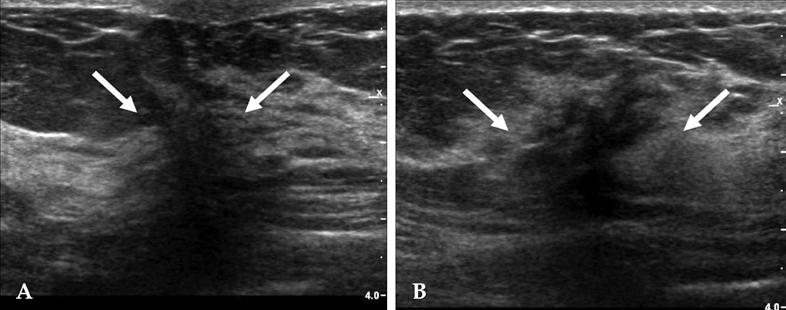

PASH presented as a circumscribed solid mass, with hypoechoic texture with or without heterogeneity, and a parallel orientation. The features of small, internal cysts or vascular channels and no calcifications can be used to differentiate the lesions from fibroadenomas. A core needle biopsy misdiagnosed PASH in 13 cases out of 28 cases and vacuum-assisted biopsy correctly identified PASH in all 3 cases.

PASH表现为边界清晰的实性肿块,呈低回声,质地均匀或不均匀,且呈平行方向。小的内部囊肿或血管通道以及无钙化的特征可用于将病变与纤维腺瘤区分开来。28例粗针活检中有13例误诊为PASH,3例真空辅助活检均正确识别出PASH。